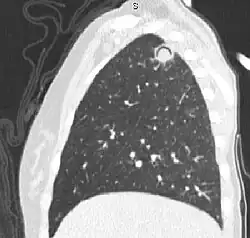

Sagittal reformat from a CT scan of the chest showing air crescent sign in a patient with invasive fungal infection. There is a rounded cavity in the apical right upper lobe, with a non-dependant soft-tissue nodule within it. Also there is some subtle ground-glass opacity surrounding the lesion.